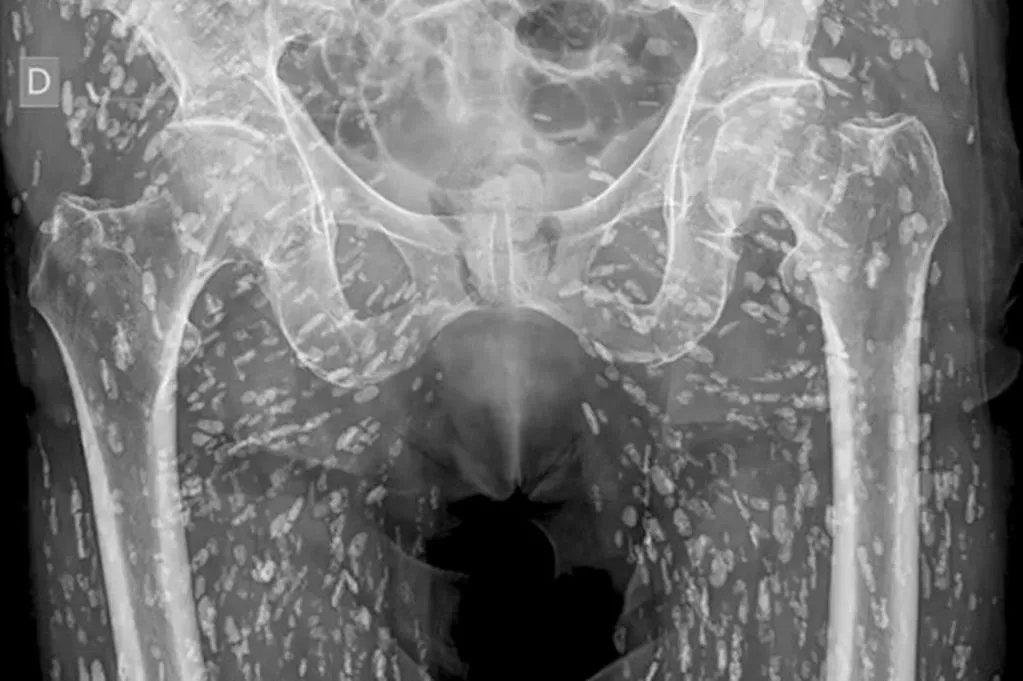

Bức ảnh cho thấy những quả trứng ký sinh nằm trong mô mềm của một người đàn ông (Ảnh: X).

Vị bác sĩ cũng đã đăng một video kèm bình luận cho thấy phần thân dưới của một người đàn ông lốm đốm những chấm trắng nhỏ, mà Ghali giải thích là hàng chục trứng sán dây vôi hóa. Những con ký sinh trùng đã xâm nhập vào cơ thể anh ta và để lại những mầm bệnh đáng sợ trong mô mềm quanh xương chậu. Lý do là người đàn ông đã phạm phải một sai lầm nghiêm trọng trong khi nấu ăn.

Bác sĩ Ghali nói trong video rằng tình trạng này, được gọi là "bệnh sán lợn", là do "ấu trùng nang sán taenia solium, còn gọi là sán dây lợn" gây ra. Ông cho biết các nang sán này có thể di chuyển "khắp cơ thể", đồng thời cho biết thêm rằng chúng xâm nhập vào các mô cơ và mô mềm sau khi người ta ăn thịt lợn chưa nấu chín hoặc sống.